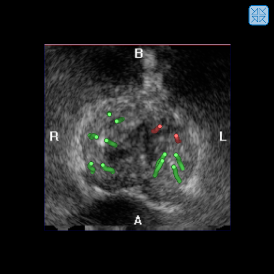

When the needle is correctly placed, the tissue sample is collected by triggering the spring needle gun. Before removing the needle, the clinician acquires a US volume containing the needle image. The needle is then automatically segmented, if present. It is projected into the reference anatomy, giving the clinician an immediate feed-back about the sampling position with respect to previous biopsies. The biopsy distribution can hence be assessed during the intervention and additional samples can be collected, if necessary. A typical interventional biopsy map is given in Fig. 12.

5.4 Multi-modal biopsy and cancer maps

After acquisition, the samples are sent to the pathologist for histological examination. The Gleason score, a visual tissue grading scale that is correlated with the aggressiveness of the carcinoma, is determined for each sample and entered into the biopsy application. A color code is used to visualize the cancer grade of a sample in the biopsy maps. This provides an instant overview over the cancer distribution for diagnosis and treatment planning.

Refer to caption

Figure 12: Biopsy maps. Fig. (a)-(c) show different views of a biopsy map with color-coded Gleason score.